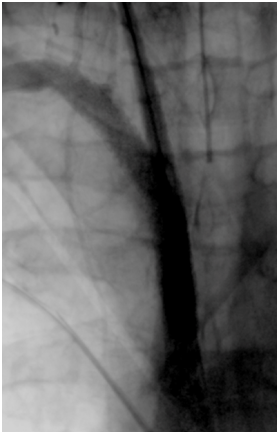

Cranioencephalic computerized tomography excluded acute ischemic lesions.CDS revealed severe stenosis of the innominate artery (PS 38 cm/s) (Figure 1), occlusion of right vertebral artery, total flow inversion of the right internal carotid artery (ICA) (Figure 2), partial endosystolic flow inversion of right CCA (Figure 3) and low amplitude anterograde flow of right external carotid artery, no significant lesions were found on the left carotid axis. Computerized tomography angiography (CTA) excluded significant carotid lesions and revealed pre-occlusive stenosis of the innominate artery by a calcic lesion (Figure 4).Surgical approach consisted of ultrasound-guided puncture of right brachial artery and surgical exposure of right CCA. Brain protection was achieved by direct clamping of the common carotid artery and subsequently carotid and axillary retrograde endovascular access was obtained. Placement of 6F introducer on brachial artery and 8F on right CCA (Figure 5). After pre-dilatation with a 4x40mm balloon (Admiral Xtreme™, Medtronic), a kissing stent technique was performed with a 6x59mm covered stent (AdvantaV12™, Getinge) on the right CCA and 7x57mm balloon-expandable stent (Visi-Pro™, Medtronic) on the right subclavian artery. At the end of the procedure direct expulsion of eventual embolic material was performed prior to declamping and a good permeability of the revascularized arteries was verified (Figure 6). Clamping time was under 1minute. The postoperative period was uneventful and patient was discharged 3days later.

Figure 6 Final angiography.